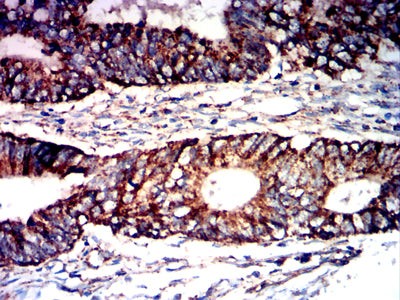

Immunohistochemical analysis of paraffin-embedded human bladder cancer tissues using PNAD mouse mAb with DAB staining